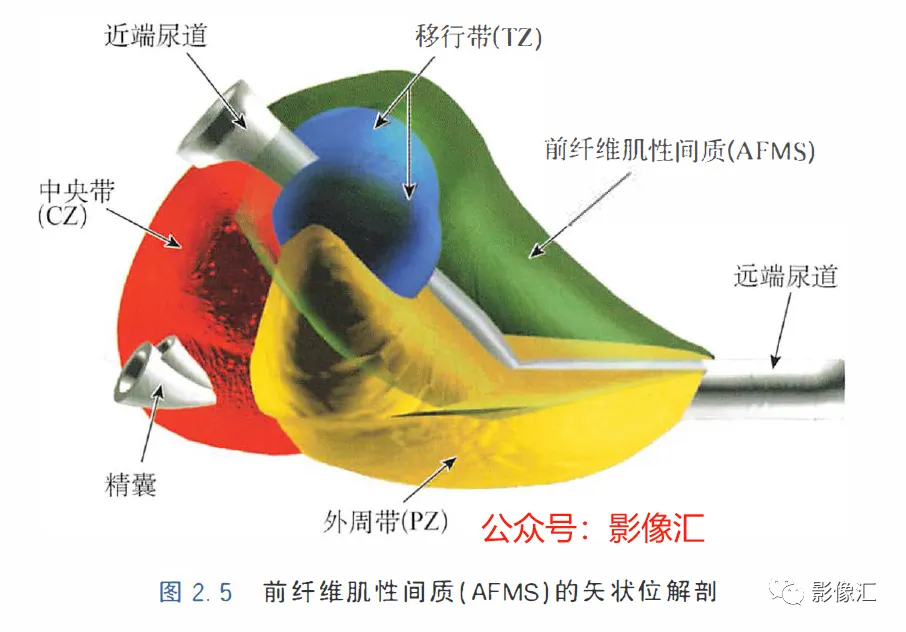

McNeal解剖模型认为前列腺根据周围不同结构环绕的关系而分为四个区域。尿道是描述整个前列腺区域解剖结构的解剖学标志。尿道由近端和远端尿道两个部分组成,每个部分约15mm长,由精阜分界。在精阜处,近端和远端尿道的走行呈35°。尿道壁由纵向走行的平滑肌纤维组成。围绕该内层的纵向肌肉层,是一层环形走行的肌层。两层平滑肌构成所谓的尿道内括约肌(IUS),其从膀胱颈延伸到尿道膜部的末端。IUS在膀胱颈的近端水平处最厚,随其向尿道膜部延伸,厚度逐渐减小。尿道膜部完整地被IUS环绕。在其前侧,前列腺内的lUS与前列腺肌性间质(AFMS)融合。两射精管走行方向与远端尿道平面平行,其开口于尿道腔内的前列腺小囊。移行带在前列腺组织中约占5%,构成两叶分别位于近端尿道两侧。其导管系统平行于尿道平面走行,止于精阜,射精管开口的近侧。移行带毗邻外周带,中央带和前列腺肌性间质,构成所谓的外科手术包膜,也就是说,确定了前列腺剜除术的外科手术平面。移行带和尿道周围腺体组织是良性前列腺增生(BPH)的发生部位。前列腺癌发生在移行带的比例为10%~20%。中央带在前列腺腺体组织中约占25%。其在前列腺底部形成金字塔形或锥形结构,在精阜水平处变窄至顶点。中央带的导管在射精管开口的两侧呈放射状走行。精囊和输精管穿入中央带形成射精管形似“精囊喙”。此区域由于缺乏前列腺包膜而成为解剖薄弱区。与射精管延续的中央带及伴行的筋膜和淋巴血管组织称为前列腺嵌入部(invaginated extraprostatic space,IES)。这是另一个解剖学上的薄弱区域,因此中央带疾病容易沿此区域播散。中央带相对发病率较低,发生在中央带的前列腺癌占5%~10%。外周带和中央带之间缺乏解剖学屏障,同时由于IES的存在,意味着前列腺尖部发生的肿瘤很容易进展到前列腺底部,并可早期造成前列腺周围间隙结构的受累。外周带约占前列腺腺体组织的70%。其包括前列腺表面的外侧、背侧和尖部,以多变的方式向腹侧延伸,与前纤维肌性间质相延续。前列腺不具有通常意义上的包膜结构,表面有一层腺样间质被称为“包膜"。前列腺“包膜”本身由纤维肌性间质构成,其在腺体周围形成一薄层结构。前列腺尖部没有这种间质层,造成一个解剖学上的蒲弱区域,称为梯形区域(trapezoidal area)。该区域腹侧以尿道膜部为界,背侧则以Denonvilliers和直肠筋膜为界,头侧以前列腺尖部(外周带)为界,尾侧则以直肠尿道肌为界。70%的前列腺癌发生在前列腺外周带。当前列腺癌起自前列腺尖部时,在早期即可通过梯形区域侵犯前列腺周围间隙。前列腺的背外侧神经血管蒂也是肿瘤易向外蔓延和侵袭的区域。AFMS约占前列腺体积的33%,是前列腺的非腺体区域,构成前列腺的前表面。在其最近端部分,其与逼尿肌和尿道内括约肌(IUS)的平滑肌纤维融合。头侧,其保持和尿道外括约肌(EUS)的关系;EUS的横纹肌纤维在该区域(前列腺尖部的前外侧)融合,构成前列腺外括约肌群。有四个“解剖薄弱“ 区域,通过这些区域,前列腺肿瘤可以生长并侵犯相邻的结构。这些区域是:精囊喙(图2. 6和图2. 17)

- 前列腺分为四个区域:移行带(TZ)、中央带(CZ) 、外周带(PZ) 和前列腺肌性间质带(AFMS)。